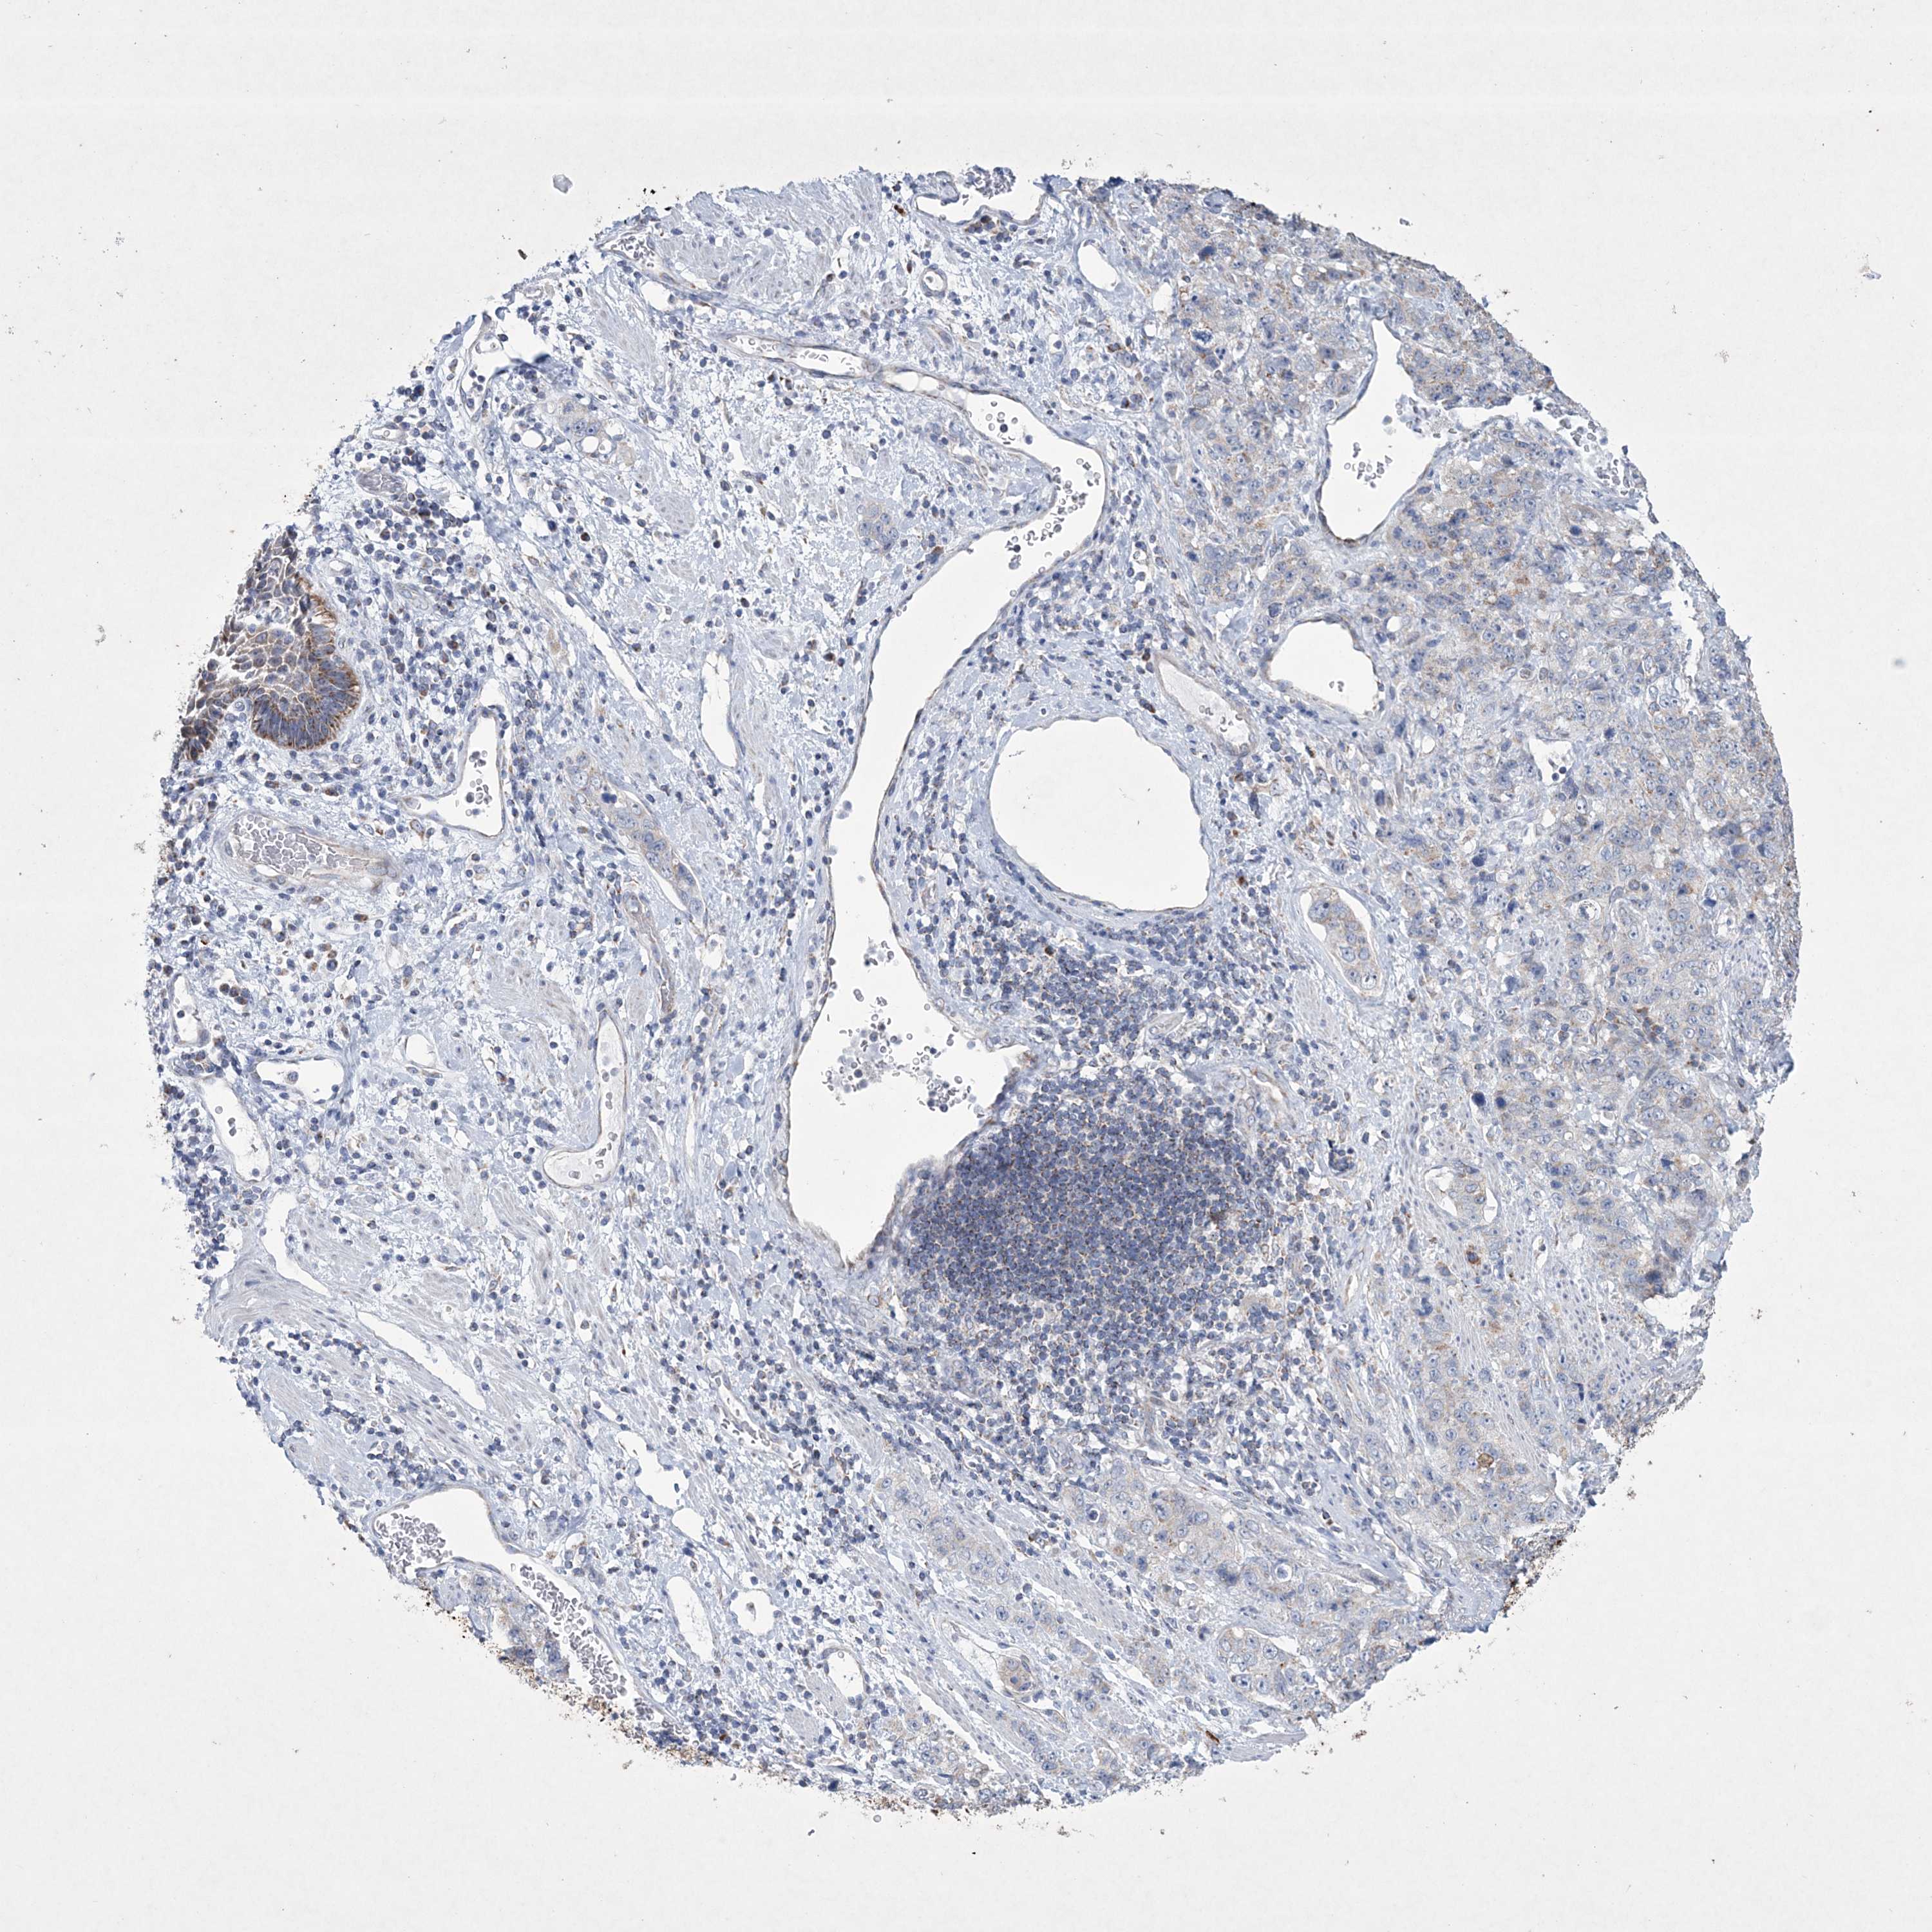

STOMACH CANCER - Protein expressioni

A mouse-over function shows sample information and annotation data. Click on an image to view it in a full screen mode. Samples can be filtered based on level of antibody staining by selecting one or several of the following categories: high, medium, low and not detected. The assay and annotation is described here.

Note that samples used for immunohistochemistry by the Human Protein Atlas do not correspond to samples in the TCGA dataset.

Antibody stainingi

Antibody staining in the annotated cell types in the current human tissue is reported as not detected, low, medium, or high, based on conventional immunohistochemistry profiling in selected tissues. This score is based on the combination of the staining intensity and fraction of stained cells.

Each image is clickable and will lead to virtual microscopy that enables deeper exploration of all samples and also displays staining intensity scores, fraction scores and subcellular localization as well as patient and tissue information for each sample.

Antibody HPA035701

Staining

High

Medium

Low

Not detected

Intensity

Strong

Moderate

Weak

Negative

Quantity

>75%

75%-25%

<25%

None

Location

Nuclear

Cytoplasmic/membranous

Cytoplasmic/membranous,nuclear

Adenocarcinoma, NOS